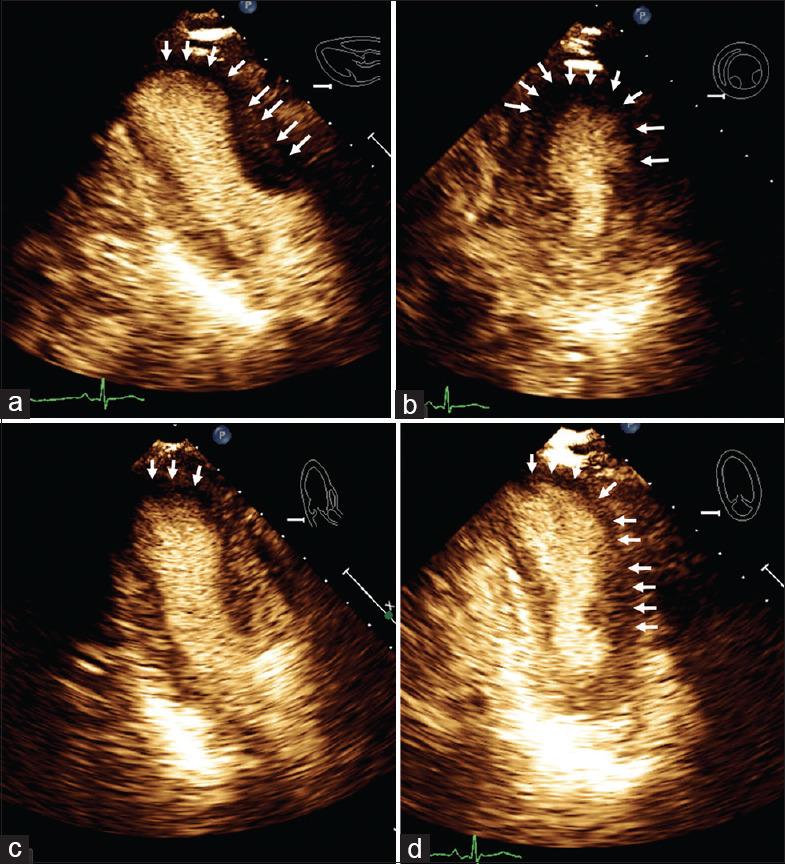

Acute coronary syndromes (ACSs) present most frequently with chest pain, but angina equivalents such as dyspnea, diaphoresis, and fatigue are not uncommon. Atypical presentations are especially seen in women, the elderly, and diabetics. Cardiac evaluation using a transthoracic echocardiogram is almost always done before or immediately after someone undergoes left heart catheterization for ACS. It provides information valuable information regarding wall motion, left ventricular systolic function, diastolic function, right ventricular involvement, pulmonary pressures, incidental valvular disease, pericardial fluid, or any other unsuspected abnormality. We describe a novel case where an atypical presentation of ACS was suspected based on the lack of intravenous contrast administered, to enhance endocardial border resolution. The use of contrast during echocardiography has been used during stress protocols to assess microcirculation during perfusion assessment studies. However, we described a reduced uptake during the acquisition of resting myocardial echocardiogram images and it was very useful to direct therapy.

急性冠状动脉综合征(ACSs)最常表现为胸痛,但诸如呼吸困难、出汗和疲劳等等效心绞痛症状也并不罕见。非典型表现尤其多见于女性、老年人和糖尿病患者。对于因ACS接受左心导管插入术的患者,几乎总是在术前或术后立即进行经胸超声心动图心脏评估。它能提供有关室壁运动、左心室收缩功能、舒张功能、右心室受累情况、肺压力、偶发性瓣膜疾病、心包积液或任何其他意外异常的有价值信息。我们描述了一个新病例,该病例基于未使用静脉造影剂以提高心内膜边界分辨率而怀疑为ACS的非典型表现。超声心动图检查期间使用造影剂已用于负荷试验方案中,以在灌注评估研究中评估微循环。然而,我们描述了在静息心肌超声心动图图像采集期间摄取减少的情况,这对指导治疗非常有用。